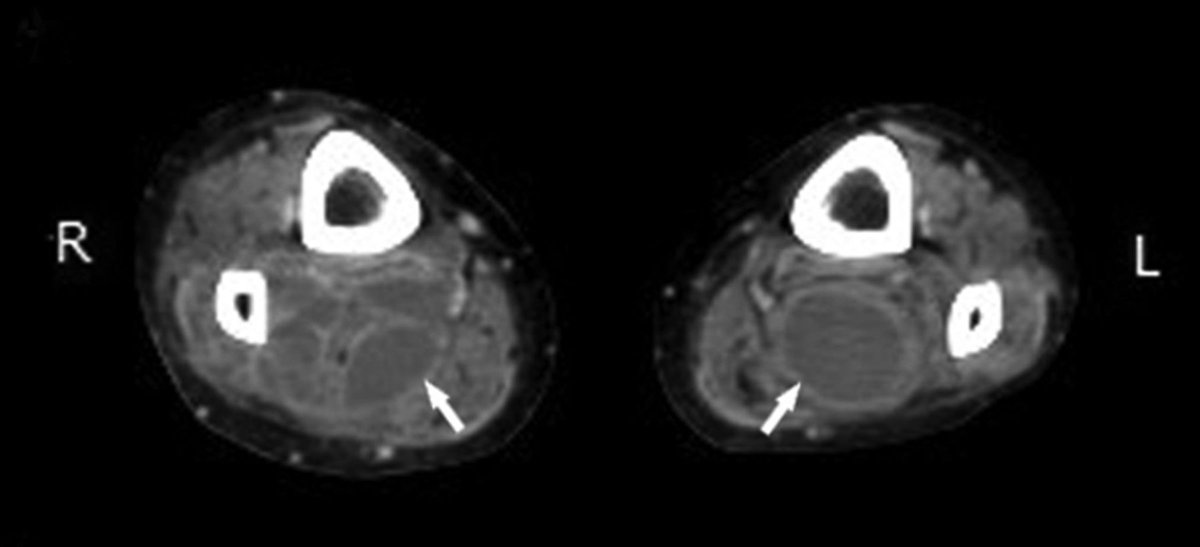

🧫JASPI Case Report (Vol. 3 Issue 4) 🦠MRSA Pyomyositis in Chronic Granulomatous Disease. 📌CT: Multiloculated gluteal & thigh abscesses. 🔬Culture: MRSA. 💊Treated with drainage + targeted antibiotics. 🔗 doi.org/10.62541/jaspi… #MRSA #ICMRDelhi #Pyomyositis #InfectiousDiseases

📌CT: Multiloculated gluteal & thigh abscesses.